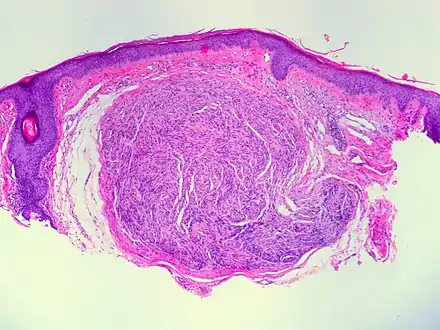

| Micrograph of a palisaded encapsulated neuroma | |

PEN is diagnosed by clinical recognition of the lesion and on subsequent histologic examination. Typically, the lesions are suspected to be schwannomas or neurofibromas clinically with PEN being an incidental finding on histology.[3]

PEN is typically diagnosed in patients between the ages of 40 and 60 years and occurs more frequently in females than males. The diagnosis of PEN may be difficult, even with confirmatory histology, due to its histological similarities with schwannomas and neurofibromas. It is imperative that the correct diagnosis is made the misdiagnosis of a neurofibroma may lead to unnecessary further investigation into associated systemic syndromes such as neurofibromatosis type 1 or multiple endocrine neoplasia syndrome.[3][4]